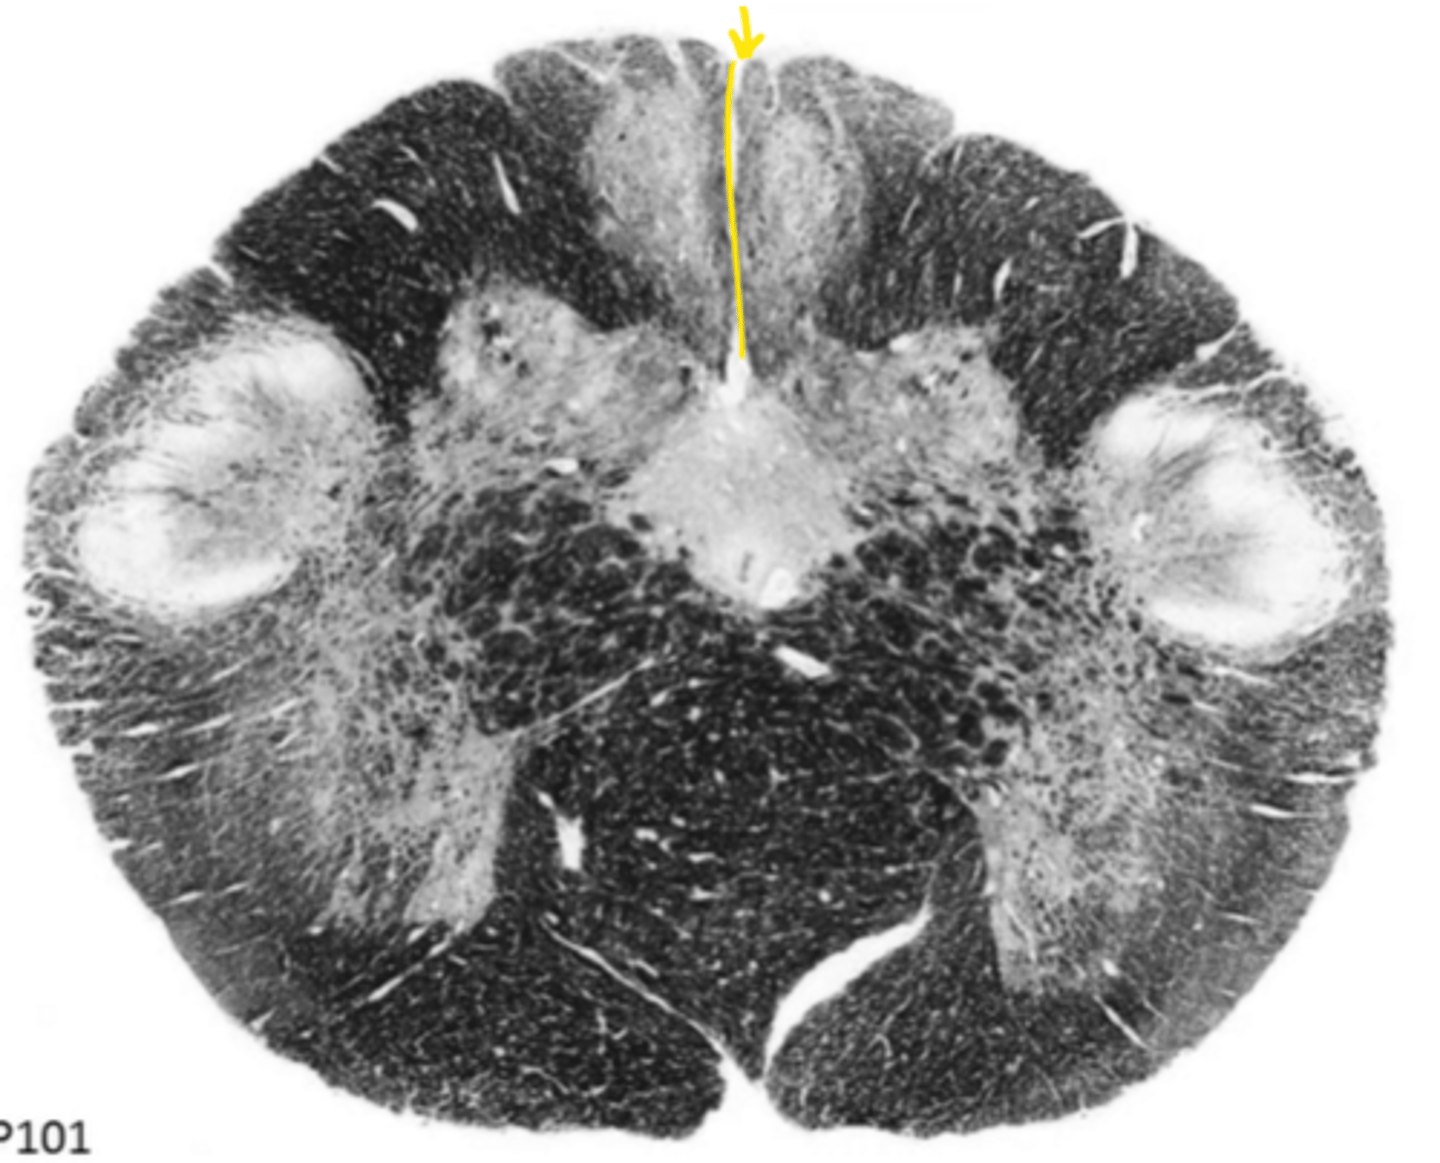

open medulla

ID the brainstem level